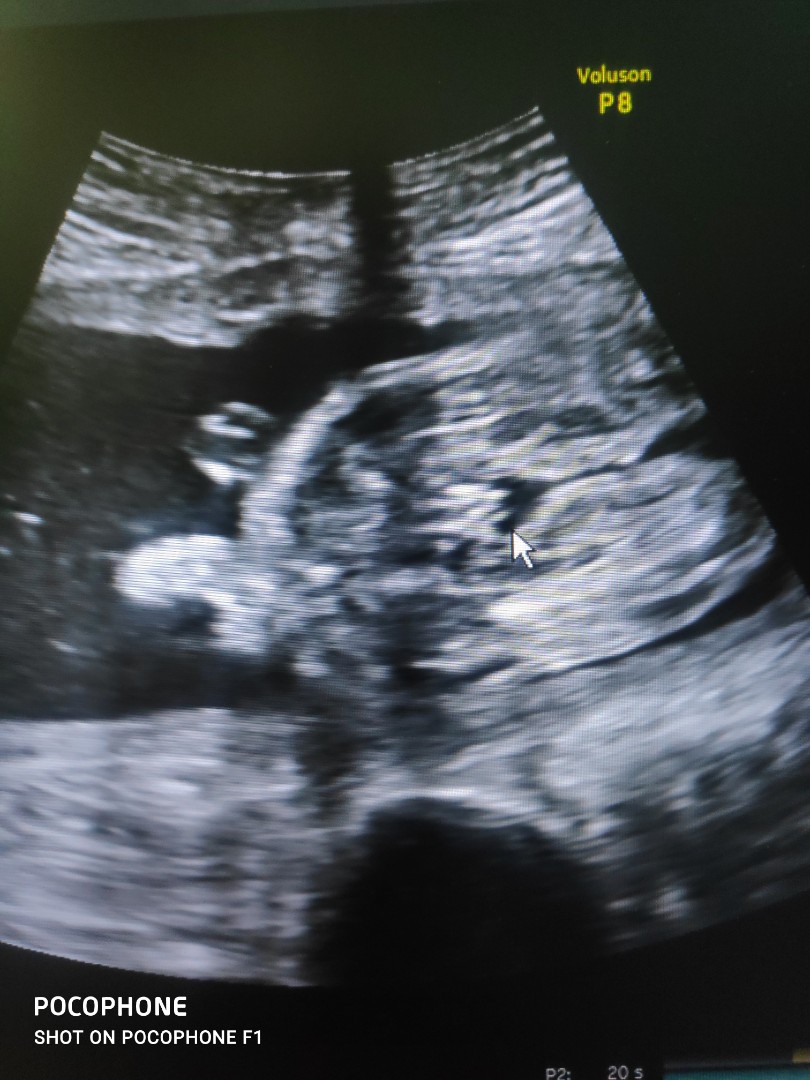

หมอบอกชาย มีสิทธิ์จะเป็นหญิงบ้างไหมคะ

อายุครรภ์ พึง14 สัปดาห์ จะเห็นเพศชัดขนาดนี้เลยหรอคะ

น่าจะตามที่หมอบอกค่ะแม่จู๋โผล่แล้วค่ะ

ชัดขนาดนี้ไม่เป็นผู้หญิงแล้วหละค่ะ

ชัดอยู่นะคะ เหมือนผู้ชายเลยค่ะ

ถ้าเพศชายจะเห็นได้ก่อนเพศหญิง